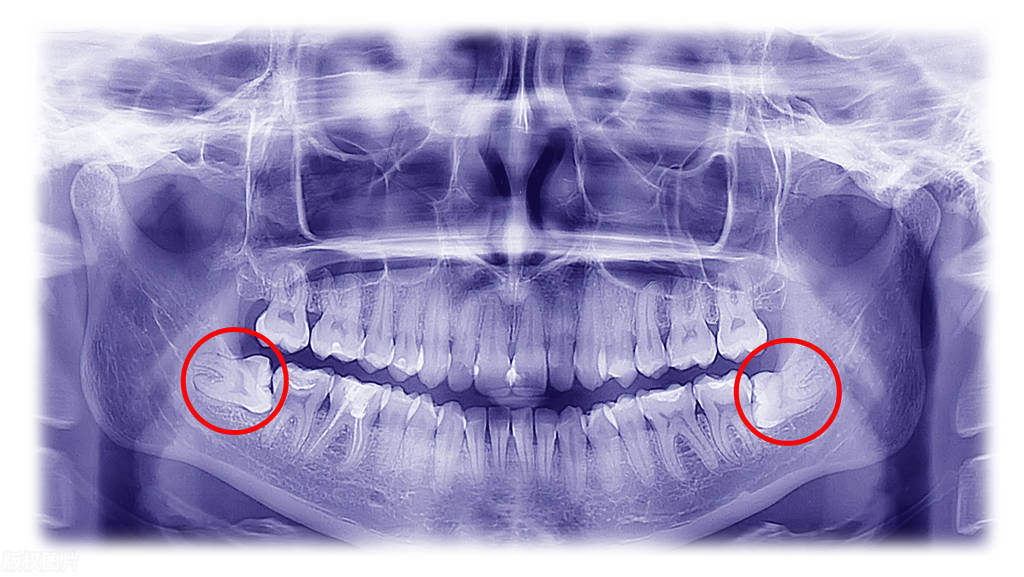

去医院检查后,医生说他的智齿是 水平阻生智齿 ,建议先拔2颗,拿工具又割又锤了2个多小时才拔下来,中间还出了很多血,又是止血又是补打麻药的。

水平阻生智齿

1、阻生智齿

阻生智齿,指的是在生长过程,受到阻碍不能正常萌出的智齿。当智齿长得不正的时候,就会有多重危害,比如反复发炎引起疼痛,横着长把前面的牙齿顶歪或者顶坏。因此临床上建议,如果智齿是阻生,在还没有完全长出来的时候,就可以进行预防性的拔除。

阻生智齿的多种类型